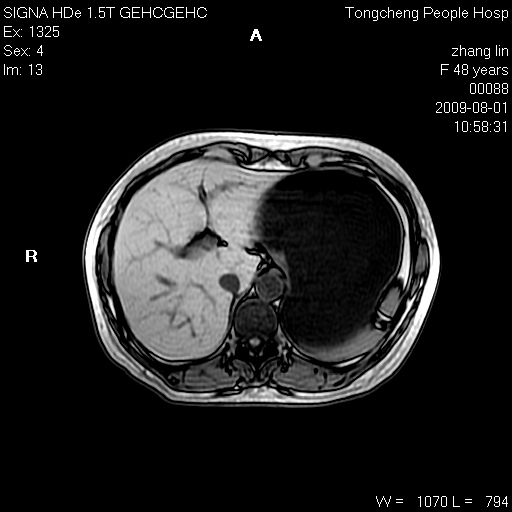

女,48岁。健康体检,彩超发现右肾占位性病变。平素健康。

临床诊断:右肾占位性病变,性质待定(囊肿?肿瘤?)。

上中腹部mr平扫+增强扫描,图像如下:

右肾上极见一类圆形病灶,t1wi呈等信号t2wi呈等高混杂信号,三期增强无强化,边界清---考虑囊肿出血。

同反相位均表现为等信号,病变无强化,考虑含蛋白的囊肿可能,弥散加权相或许有些帮助,

慢性胆囊炎